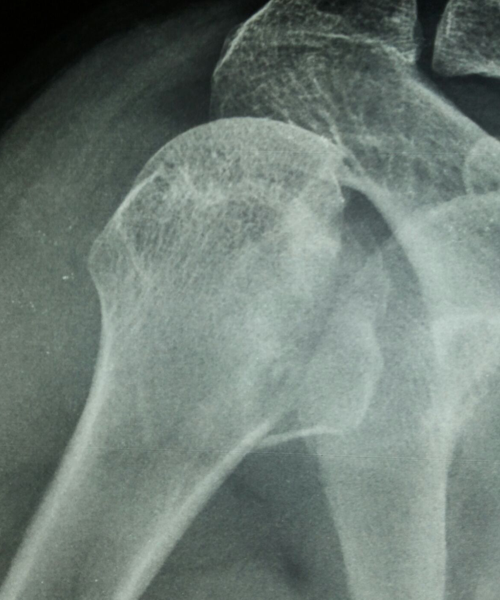

Case:18 Comminuted Fracture Upper Humerus

Female 65 years sustained fall in the house had displaced fracture of head of left Humerus with displaced fragment of greater tuberosity was treated with open deduction and philos plate fixation.

Pre-Op-Xray